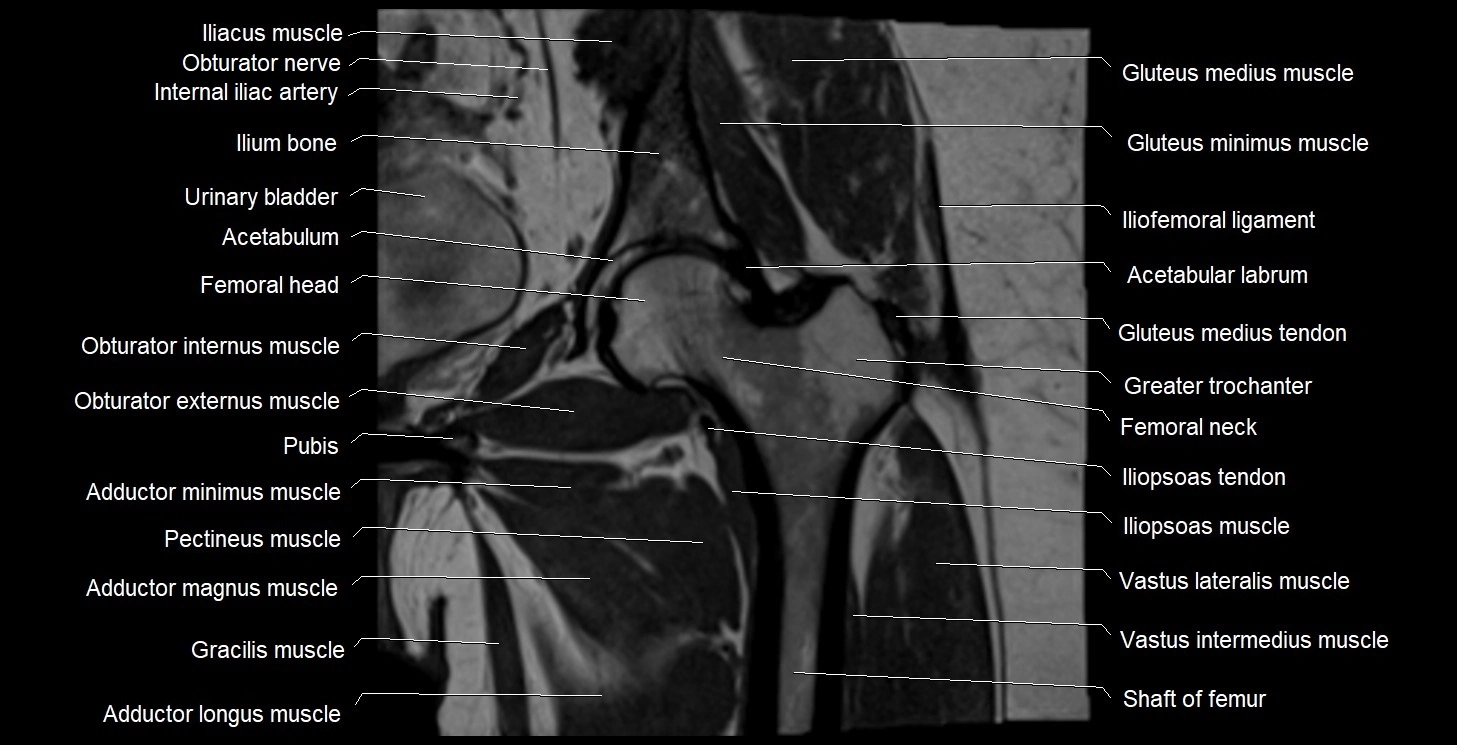

- Acetabulum

- Adductor brevis muscle

- Adductor longus muscle

- Adductor magnus muscle

- Adductor minimus muscle

- Gluteus medius muscle

- Gluteus medius tendon

- Gluteus minimus muscle

- Gluteus minimus tendon

- Gracilis muscle

- Greater trochanter

- Head of femur

- Iliofemoral ligament

- Iliopsoas muscle

- Iliopsoas tendon

- Ilium bone

- Neck of femur

- Obturator externus muscle

- Obturator internus muscle

- Obturator nerve

- Pectineus muscle

- Vastus intermedius muscle

- Vastus lateralis muscle